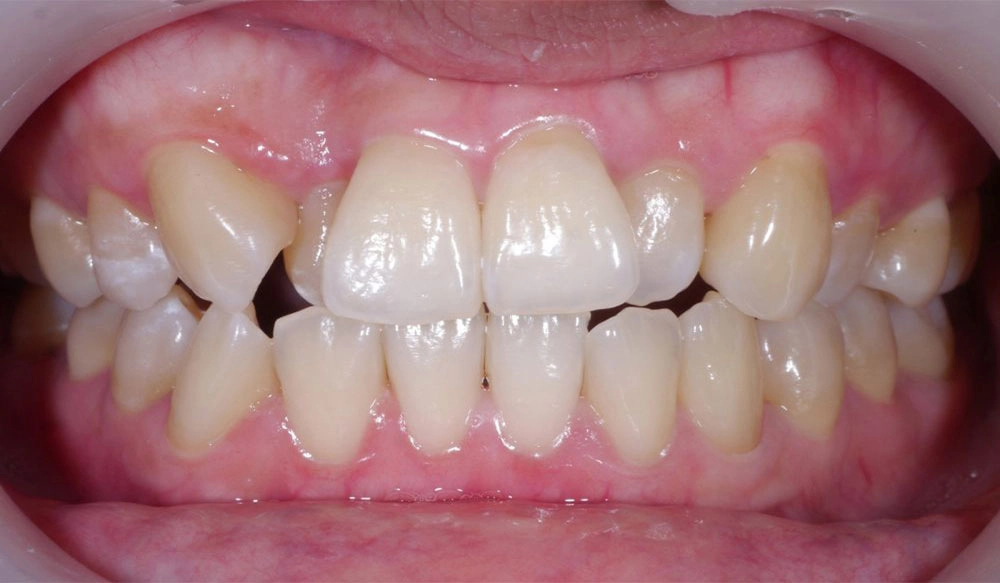

Crowding

Crowding is the condition in which there is a discrepancy between tooth size and space available for the teeth to be aligned in the dental arch

Patient Information:

Age: 17

Gender: female

Invisalign Treatment Option: Invisalign Comprehensive

Total Treatment Time:

29 months